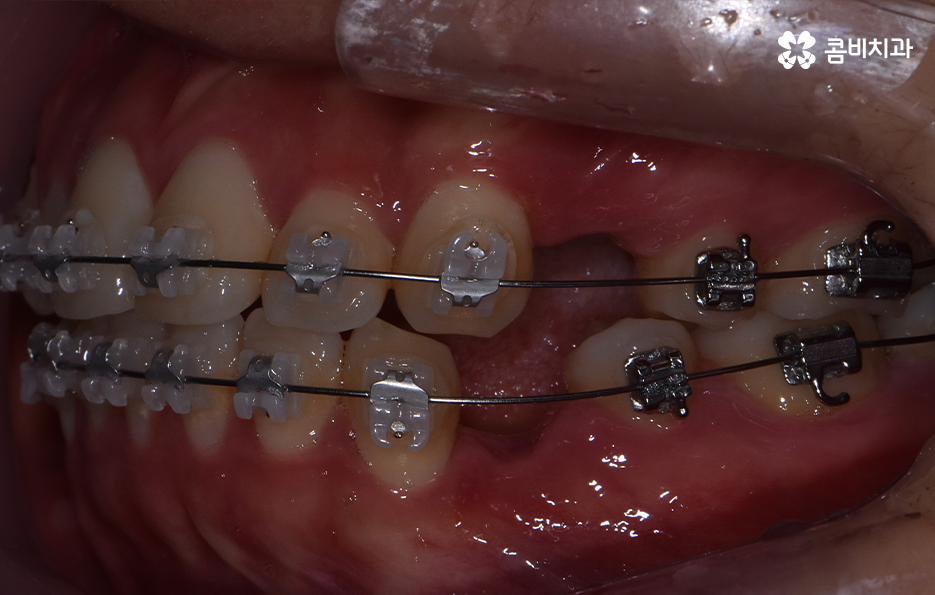

오늘은 돌출입발치교정 통해서 치열도 가지런하게 교정하고 얼굴형의 변화뿐 아니라 교합까지 잘 맞물려서 건강하게 치아교정을 하는 방법에 대해 알아볼 거예요

보통 치아교정을 통해 눈에 띄게 얼굴 변화를 느끼게 되는 경우는 쉽게 말해 발치를 통한 교정으로 볼 수 있어요. 그 이유는 치아를 발치하게 되면 발치한 만큼의 공간이 악궁에서 축소가 되기 때문에 그로 인해 얼굴라인이 갸름하게 변하게 되거나 돌출입발치교정 같이 돌출입의 개선이 되는 거예요

보편적으로 돌출입발치교정 통해 치료가 진행되면 돌출입이 개선되는 경우가 대부분이지만 앞니의 각도나 턱뼈와의 상관관계 등을 고려할 때 치아교정 만으로는 치료의 만족도가 높지 않은 경우도 있는데요. 이 경우 외과 수술이 동반되어야 할 수 있습니다.